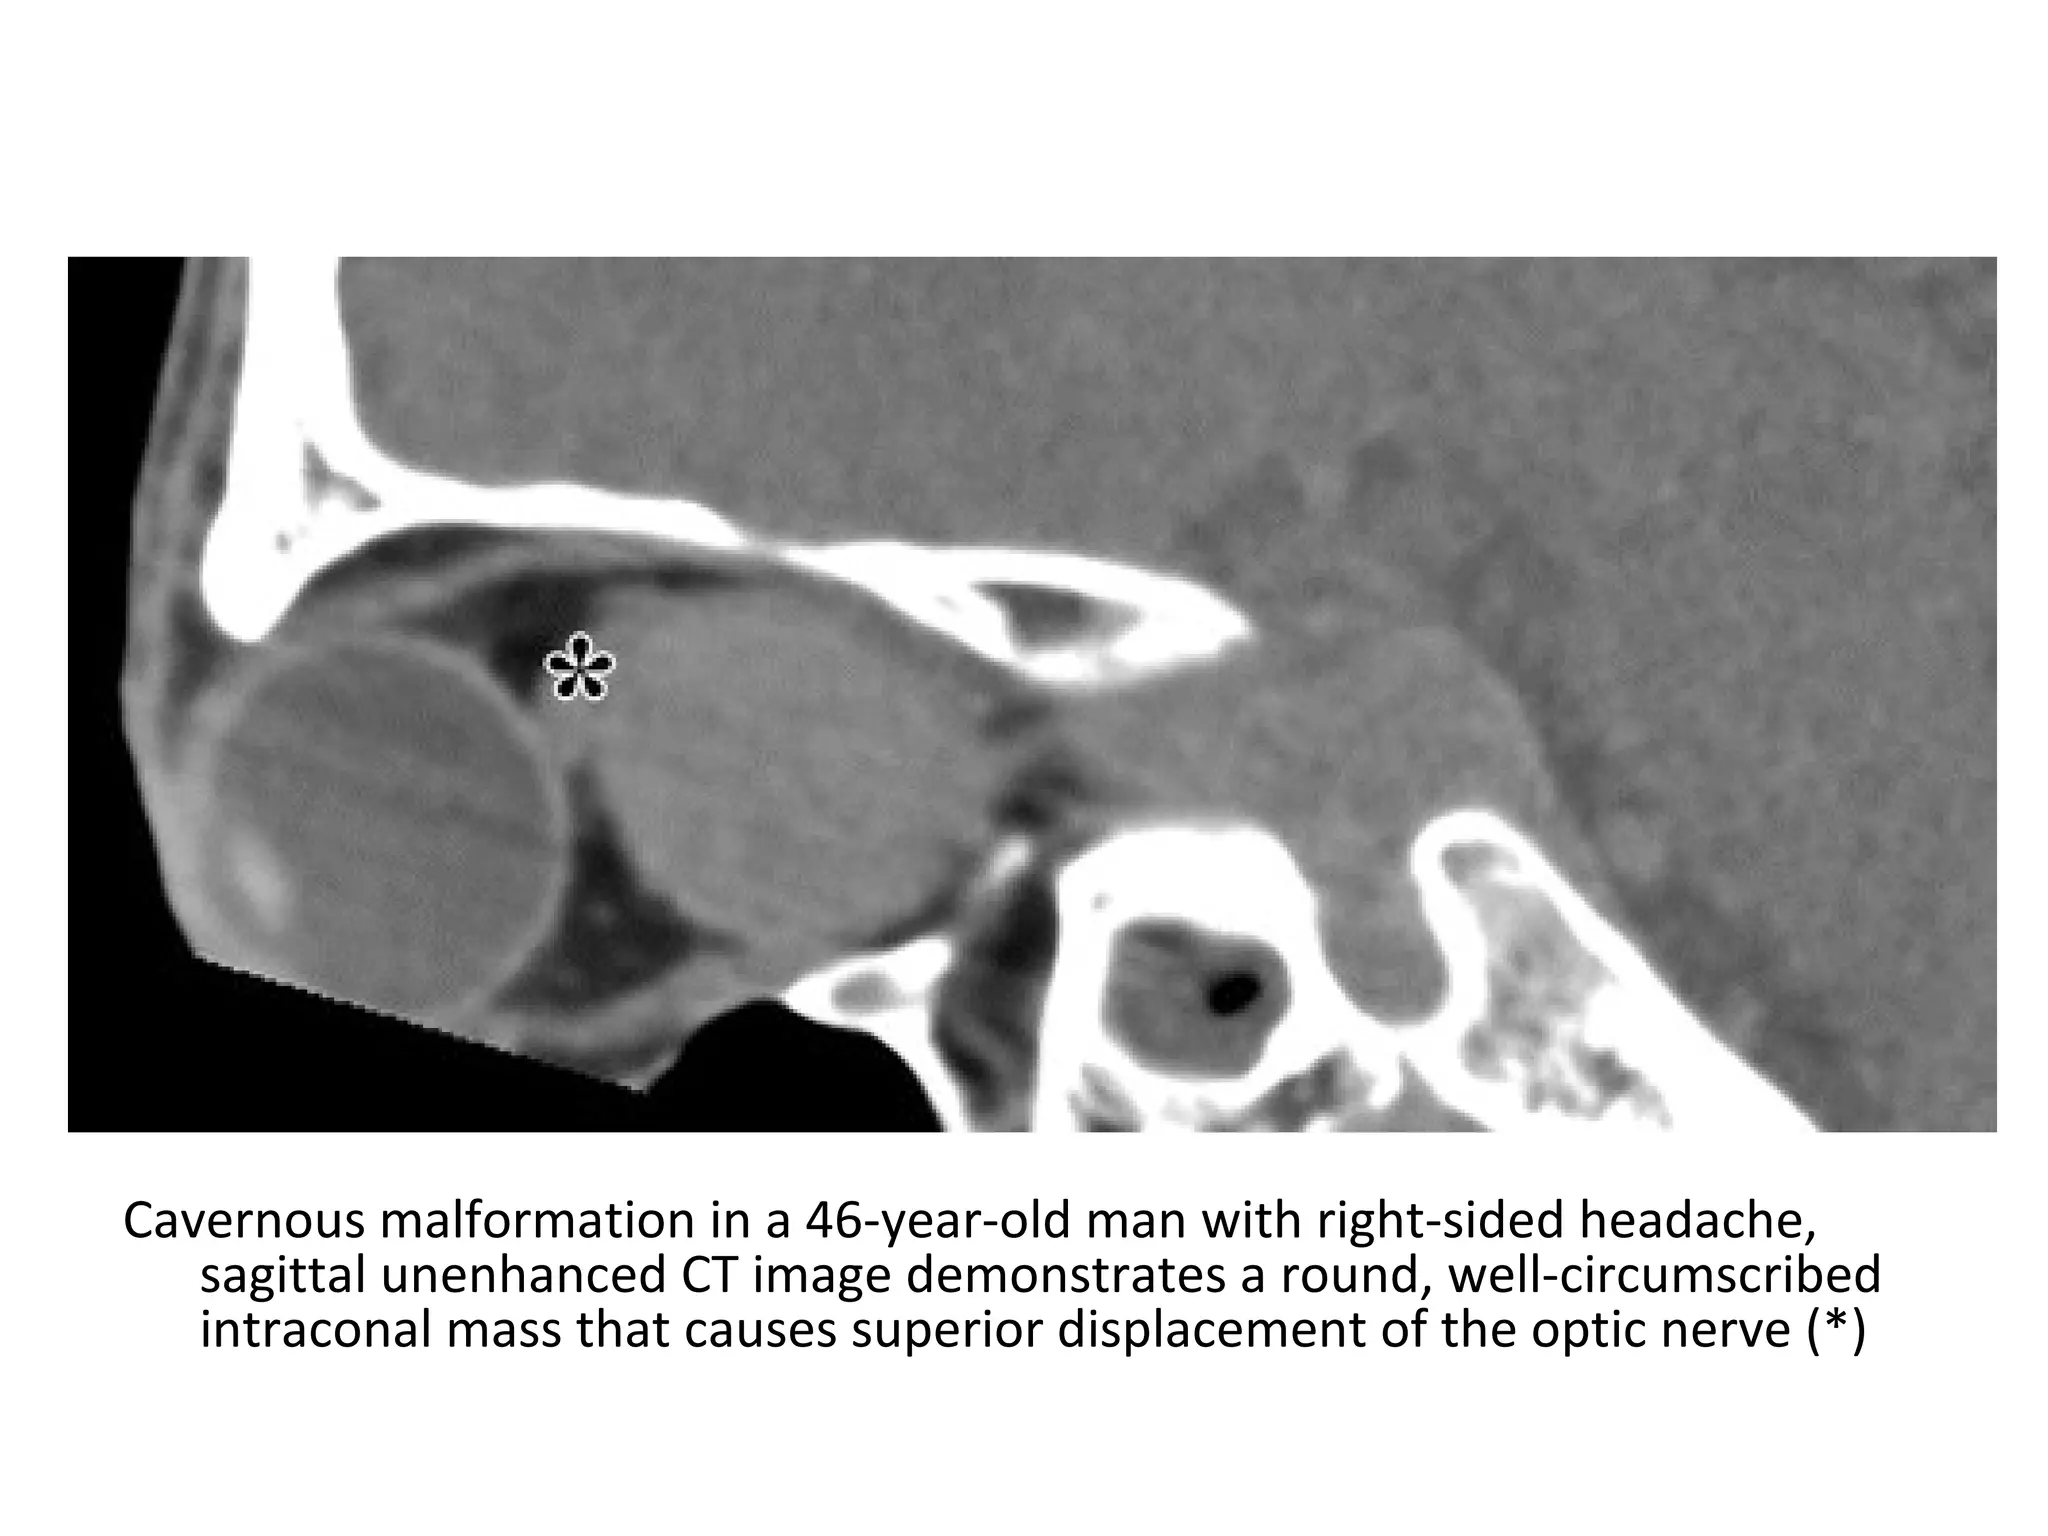

Cavernous malformation in a 46-year-old man with right-sided headache,

sagittal unenhanced CT image demonstrates a round, well-circumscribed

intraconal mass that causes superior displacement of the optic nerve (*)

b) Radiographic Features:

1-CT:

-Well circumscribed , somewhat

hypoattenuating compared to muscle , which

gradually fills in following administration of

contrast